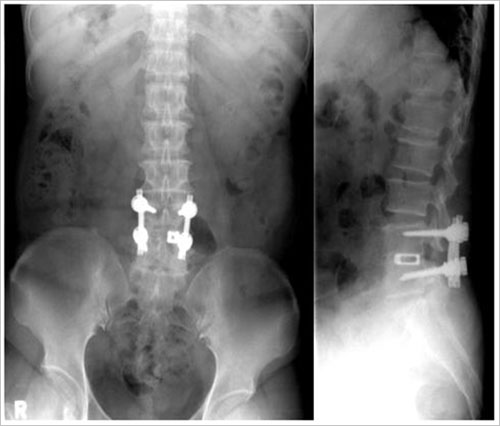

< ÈÄ¹æ °¨¾Ð¼ú ÈÄ ÈĹæ Ãßü°£ À¯ÇÕ¼ú ¹× °íÁ¤¼úÀ» ½Ç½ÃÇÑ »çÁø >

< ÀÏÃø Á¢±Ù¿¡ ÀÇÇØ ¾çÂÊÀÇ Ã´Ãß°ü ÇùÂøÀ» °¨¾ÐÇÏ¿© ¼ö¼úÇÑ »çÁø >